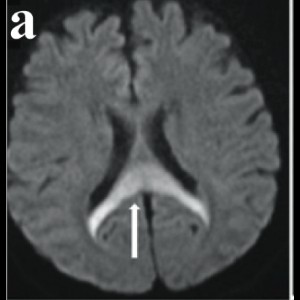

Wine Glass Sign and Empty Delta Sign: A Rare Imaging Presentation of Postpartum Encephalopathy in Dehydration

Wine Glass Sign and Empty Delta Sign: A Rare Imaging Presentation of Postpartum Encephalopathy in Dehydration

Wine Glass Sign and Empty Delta Sign: A Rare Imaging Presentation of Postpartum Encephalopathy in Dehydration

Wine Glass Sign and Empty Delta Sign: A Rare Imaging Presentation of Postpartum Encephalopathy in Dehydration